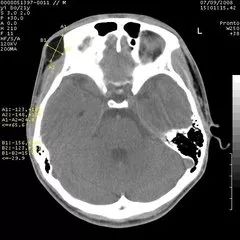

CT头颅扫描图像

从“计算机体层摄影”这个名词可以看出,CT实际上也是一种体层摄影,但它在成像技术上却有了突破性进展。它有了完善的扫描机架,扫描角度极大提高,轻易地实现了横断面的体层摄影。更突出的是,CT首创性地将高性能计算机技术应用到影像领域,又使用高性能的探测器同步检测X线衰减信息,影像精度空前提高,层面结构清晰,完全消除了重叠对病变遮盖的问题。更难能可贵的是,CT能调节“窗宽、窗位”等手段(后续再介绍,也可参阅我写的科普专著),使密度分辨力得到了空前的提高,原本在密度对比方面差别很小的器官组织,也可以在CT上显示出浓淡不同的清晰影像。比如,对于头颅,CT不仅能够看清颅骨的结构,而且能够看到大脑的内部结构如灰质、白质和脑室等。因此,CT极大地拓宽了X线诊断的适用范围。